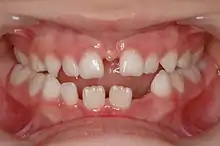

An alveolar cleft is a failure of the premaxilla to fuse with the upper jaw leaving a defect in the bone. It is common in people with cleft palate and is also associated with holes between the mouth and the nose that affects speech, and allows fluid to move into the nose when eating and drinking.

Surgeries on the roof of the mouth early in life typically close the larger hole between the mouth and the nose (caused by the cleft in the palate) but do not repair the defect in the bone, or any holes further forward between the palate and the upper lip. About the age of 8, just before the eye teeth are about to erupt into the bone defect (the cleft), braces are used to first widen the upper jaw, and position the premaxilla. Then, a surgery places bone or a bone substitute in the defect to allow the premaxilla to fuse to the rest of the maxilla, provide bone for eruption of the canine, and close any remaining holes between the mouth and nose. If completed early, the canine teeth will erupt into the mouth with good bone support and remain healthy.

Alveolar cleft grafting is used primarily to allow the eruption of the maxillary canines into the mouth between the ages of 8–13 years old. It is also used to close oranasal fistulas, stop fluid reflux into the nose, improve speech, support the maxillary lateral teeth, and stabilize the jaw for orthodontics or orthognathic surgery.